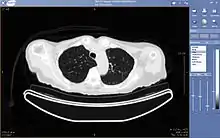

La téléradiologie consiste en la consultation et l'interprétation d'images radiologiques ou échographiques à distance.

L'activité de téléradiologie se divise en deux activités distinctes, le télédiagnostic d'une part et la télé-expertise d'autre part.